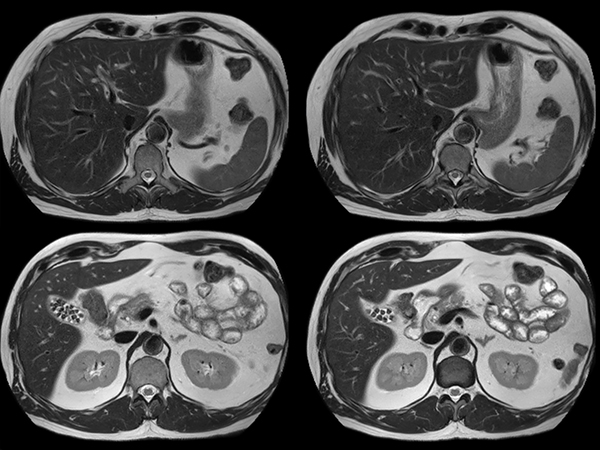

Total Torso imaging - MultiVane XD